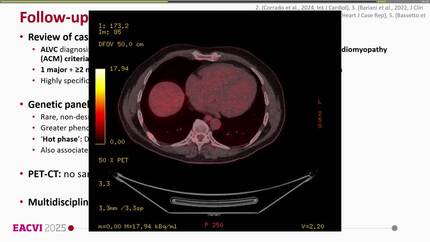

Arrhythmogenic left ventricular cardiomyopathy: a challenging diagnosis.